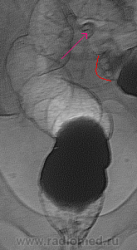

В данном случае большую роль сыграли онколог с пальцевым исследованием прямой кишки и эндоскопист с взятием биоптата, так что от меня только формальность-в последнюю очередь. По поводу красной стрелки это пузырьки газа с отграничением контраста, а то что указано стрелкой скорее всего остаточная перистальтика, на остальных снимках нет чего такого подобного, да и под скопией такое очень заметно.

С пузырьками газа можно согласиться, я их «до кучи» обвёл, хотя по этой миниатюре…, но у Вас были нормальные снимки. А вот перистальтика, с такой крутизной и углами… непохоже.

Ректо-сиггмоидный угол особенно-хорошо виден в полжении Шассара-Лапине, и главное не требует от врача-рентгенолога никаких усилий.

Так ведь Валентин Львович и в 1й косой прекрасно получается